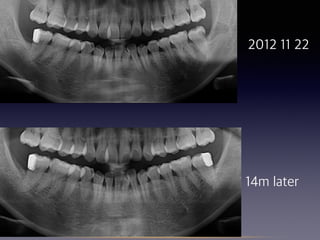

#31 partial pulpotomy

follow-up

(38 female)

2012 08 29

2012 11 22

14m later

16m later